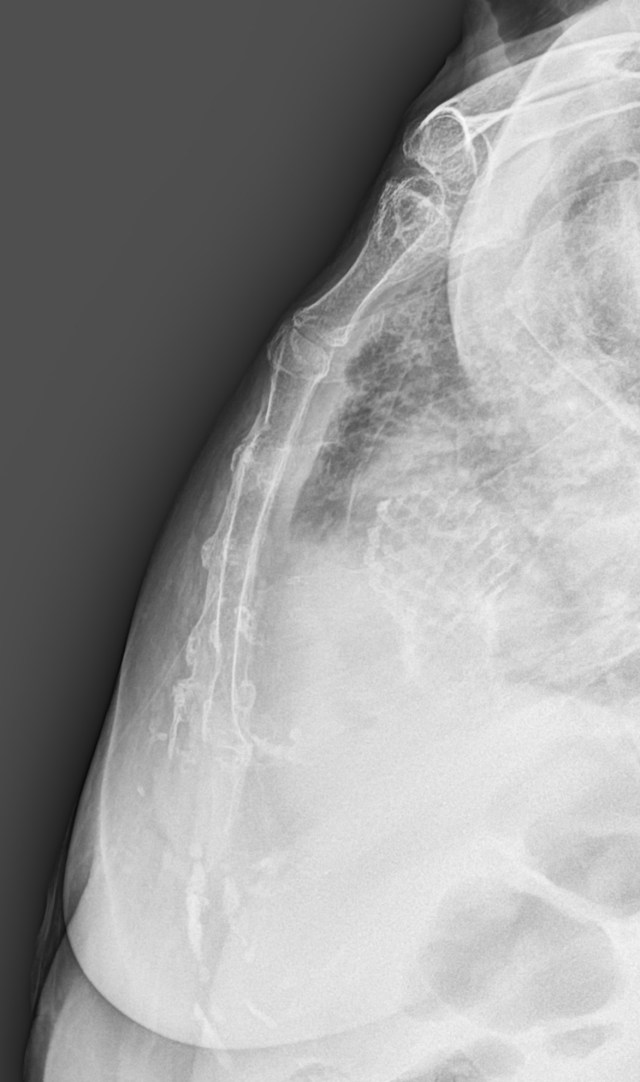

흉골 측면영상에서 upper body 부위의 anterior cortex 일부가 연결되지 않아보이는데, 뚜렷한 골절선이 보이거나, posterior cortex쪽에는 별다를 소견이 보이지 않았습니다.

sternum oblique view에서는 별다른 골절의심소견이 보이지 않았고, 환자는 좌측 늑골 아래쪽의 흉벽에 멍이 들어있으면서 해당부위에 통증을 호소하였지만, 정작 흉골부위에는 별다른 통증을 호소하지 않았습니다.

흉골의 측면 단순촬영 영상에서 뒷쪽 cortex는 잘 연결되어 있는 것으로 보임에도 불구하고, 실제로는 뒷쪽 cortex까지 골절선이 연장되어 있었던 것입니다. 이렇게, 단순촬영 영상만 가지고는 흉골골절을 정확하게 evaluation하는게 어려운 경우를 저도 종종 겪고 있습니다.